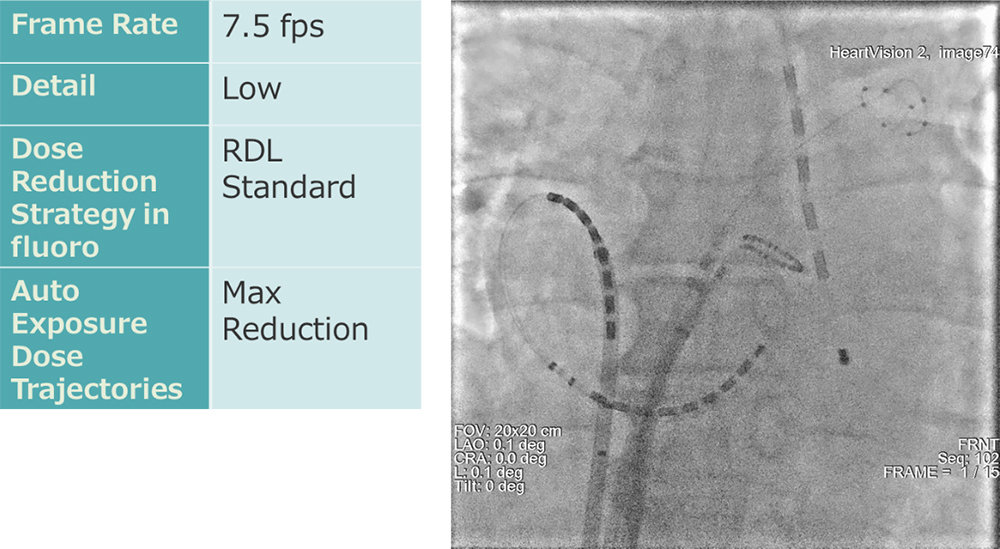

② 冠動脈領域

冠動脈領域の検査・治療における透視条件は、フレームレート7.5fpsに設定しています。当院での透視条件設定を表に示します。この設定条件において、指頭型電離箱を用いて臨床と同じ配置での線量率を計測しました。FOV20cm、SID100cm、PMMA20cmでの患者照射基準点における透視線量率は6.74mGy/minでした。既存の他社装置の場合では、透視フレームレート設定を7.5fpsに小さくすると残像が目立つ傾向が強いため、稼働前に滑らかな動作とノイズのバランスの良い動画の設定を行っています。線量を抑えた設定にも関わらず、透視画像にて既存他装置に引けを取らない視認性を実現しています。

IGS620_kurume_05.jpg

冠動脈撮影条件:7.5fpsでも視認性が保たれている